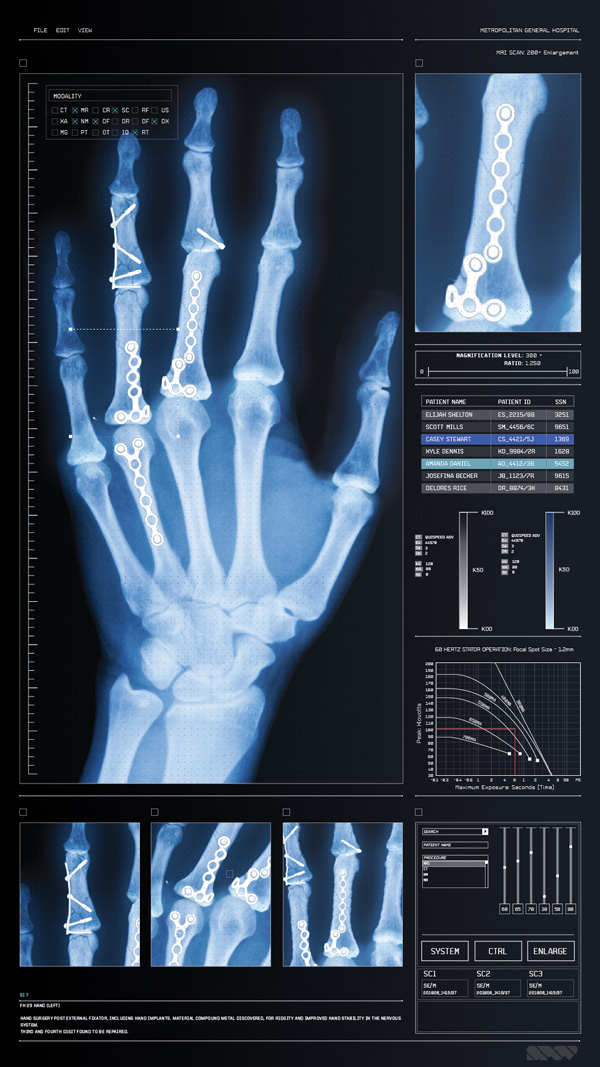

The art department also supplied them with a lot of the reference they needed for looks – ultrasound output, X-ray images and MRI scans. SPOV sourced some PACS screens as well, as samples of the standard Picture Archiving and Communication System that medical staff use to compile databases of all kinds of data.

Achieving the authenticity required in their brief meant following through on all details in a genuine way, so that everything fit in and would satisfy the fans and geeks. The small details, colours, textures, views and bits of text aren’t added gratuitously for effect, but appear as they would on real imagery for screens in a hospital. “Actually, we had a secret advantage in that our former studio manager at that time was preparing to be a nurse. She would look over our work and tell us what looked out of place or was missing – just what we needed to help sell the images,” said Allen

Nevertheless, instead of looking creepy or frightening, the results are strangely beautiful and pull the viewer toward the inner world of brains, bones and blood vessels. This look is no accident. SPOV’s main pipeline is based on Cinema 4D used together with After Effects for compositing – tools SPOV has used for years on nearly all projects and which nearly all of their artists are very familiar with.

Looking authentic and attractive in isolation is one thing, but Allen is especially pleased with the way the images look in the movie – not just on darkened sets where they glow against a black background but also in fully lit scenes where they integrate completely into the everyday world of the hospital. “Cinema 4D’s tools don’t get in the way of the creative process," he reflected. "It helps us quickly identify the most efficient route to achieve the result we’re seeking – from revolutionary flying vehicles or fantastic game characters, to something as real as an X-ray or MRI scan – and to cut down on iteration time.” www.spov.tv